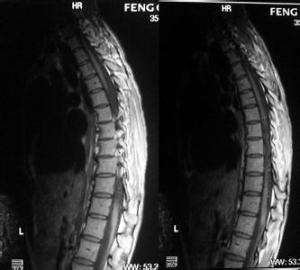

第Ⅳ型脊髓血管畸形为硬膜内脊髓周围动静脉瘘,其病变实质为硬膜内直接由脊髓前动脉供应的动静脉瘘。动静脉瘘及其回流静脉位于脊髓外方,病变并未蔓延到脊髓内。本型又分为ⅣA、ⅣB、ⅣC3个亚型。这些病变由髓内动脉(或偶尔为脊髓后动脉)和硬膜内回流静脉间的血管直接吻合组成。